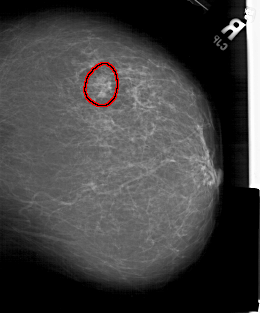

A_1583_1.RIGHT_MLO

RIGHT_CC LINES 5311 PIXELS_PER_LINE 4411 BITS_PER_PIXEL 12 RESOLUTION 43.5 OVERLAY

FILE: A_1583_1.RIGHT_CC.OVERLAY

TOTAL_ABNORMALITIES 1

ABNORMALITY 1

LESION_TYPE MASS SHAPE IRREGULAR MARGINS ILL_DEFINED

ASSESSMENT 4

SUBTLETY 4

PATHOLOGY MALIGNANT

TOTAL_OUTLINES 1

BOUNDARY